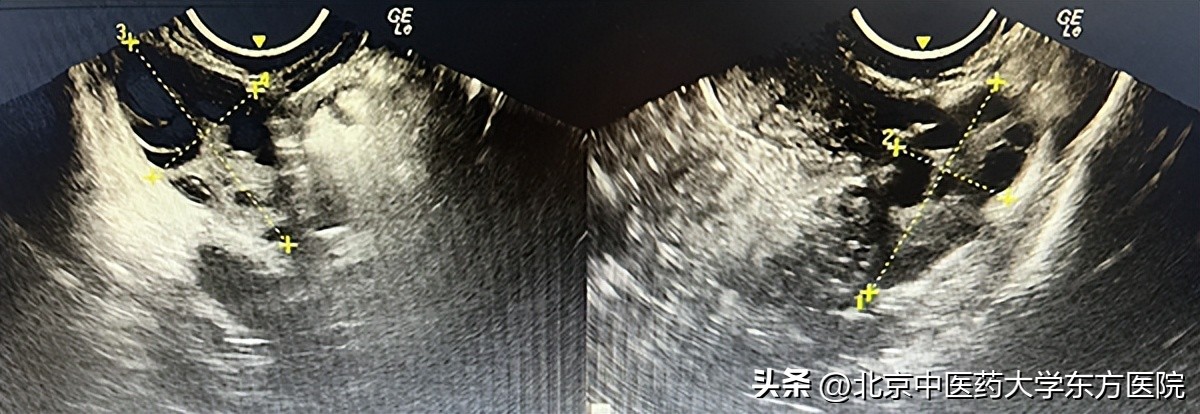

2.妇科B超:卵巢多卵泡改变。

妇科经阴道超声出现双侧卵巢多卵泡改变(一圈小卵泡,像项链一样,形成“项圈征”)无成熟大卵泡,故排卵障碍。